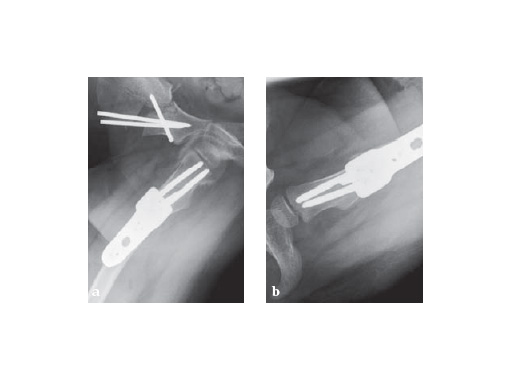

Postoperative x-ray with planned correction

Fig. 1-2

Fig. 1

X-ray after 7 weeks, postoperative treatment with hip spica due to triple OT show good healing

Fig. 2

X-ray after 11 weeks, in turn the child can run well. The triple OT is now planned on the left!